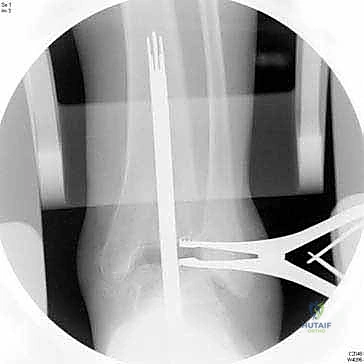

3. تحضير العظام باستخدام أدوات التوجيه

هنا تبرز روعة نظام INBONE™. يتم استخدام أدوات توجيه خاصة (Jigs) لضمان المحاذاة المثالية. يقوم الجراح بإزالة الأجزاء التالفة من غضروف وعظم الظنبوب (Tibia) والقعب (Talus) بدقة متناهية بالملليمتر.

4. إعداد القناة النخاعية وتركيب الساق (Stem)

يتم عمل ثقب دقيق في القناة النخاعية لعظمة الساق. يتم إدخال القطع المعيارية (Modular Stem Pieces) واحدة تلو الأخرى حتى يتم تحقيق التثبيت العميق والمستقر داخل العظم. هذا هو سر قوة نظام INBONE.

6. التحقق والإغلاق

يتم فحص المدى الحركي للكاحل الجديد وثباته تحت جهاز الأشعة السينية (Fluoroscopy) داخل غرفة العمليات للتأكد من المحاذاة المثالية بنسبة 100%. بعد ذلك، يتم إغلاق الشق الجراحي بغرز تجميلية، ووضع جبيرة ناعمة أو حذاء طبي واقٍ.